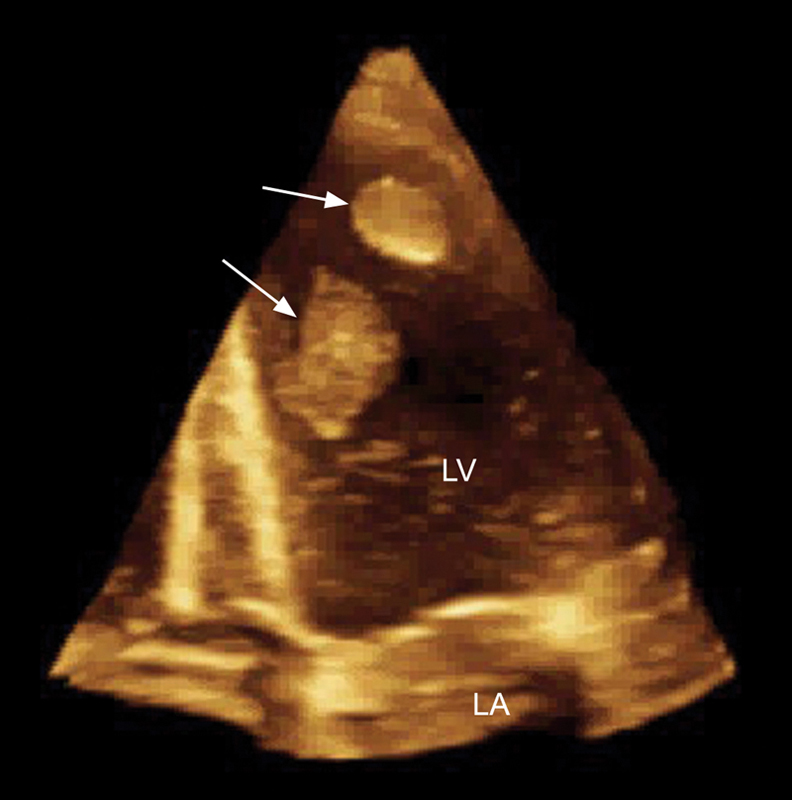

فحوصات تشخيصية لبعض امراض القلب والشرايين التاجية